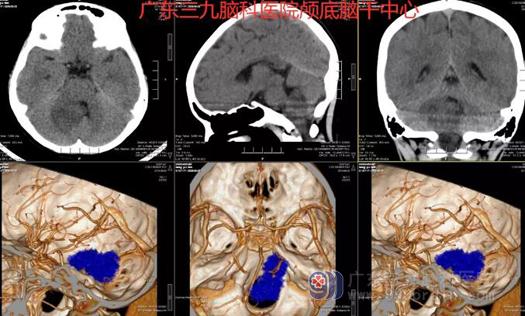

图1:术前CTA示右侧侧孔-桥小脑角区团块状占位性病变区可见少许细小血管影走行,邻近双侧椎动脉V4段(右侧为主)及基底动脉近段、右侧小脑前下动脉受压推移。